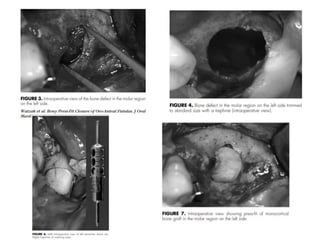

Bone Press fit closure of OAF

• The basic principle of the surgical procedure lies in press-

fitting monocortical block grafts into the bone defect to

ensure primary stability.

Watzak G, Tepper G, Zechner W, Monov G, Busenlechner D, Watzek G. Bony press-fit closure of oro-antral fistulas:

a technique for pre-sinus lift repair and secondary closure. J Oral Maxillofac Surg. 2005;63(9):1288‐1294.

Indications

•If OAF > 10 mm

•OAF with planned sinus floor elevation

•OAF along neighboring root surface extending into maxillary sinus

•Chronic OAF with multiple unsuccessful attempts of closure

Bone graft

•Iliac crest, chin, retromolar area, zygoma, lateral wall of sinus

•Autografts better option than allograft

AUTOGRAFTS FOR CLOSING OAFS

Procedure is indicated in closure of defects larger than 10 mm

or in the case of failure of conservative methods.

• Autografts harvested from:- extraction socket,

retromolar area,

zygomatic process,

chin

auricular & septal cartilage

Distant sites like the iliac crest